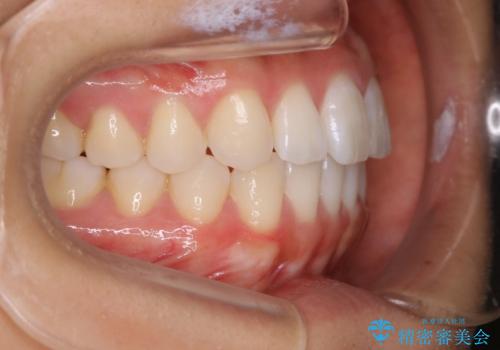

インビザライン矯正 前歯のすきっ歯を治したい

- 上顎の前歯のすきっ歯を治したいとのことで来院されました。

前歯の隙間を閉じる矯正治療の場合、インビザライン適用症例のためインビザラインによる治療をご提案しました。

後戻り防止のため、上唇小帯切除も併用しています。

上唇と歯ぐきを結ぶひも(上唇小帯)が長いと、前歯に隙間が空いてしまうことがあります。今回は隙間を確実に閉じる目的、また矯正後に再び隙間が空かないように、上唇小帯の切除も行っています。